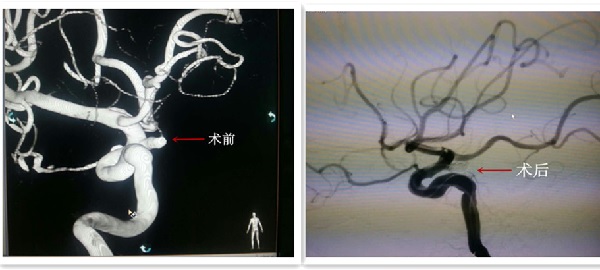

患者女性,46岁,因“突发头痛4小时”于12月15日入住我院东区神经外科。患者入院后经过完善检查后,明确诊断为左侧后交通动脉瘤。神经外科刘光宇主任通过科室讨论,认真分析患者病情后,决定行动脉瘤血管内介入栓塞手术治疗。12月18日12:30,患者由我院神经外科呼和巴特尔主治医师主刀,赵林副主任医师配合下,

于大型C臂下行后交通动脉瘤血管内介入栓塞术。经过1小时20分手术顺利完成,术后造影显示动脉瘤消失,患者恢复良好,神志清醒,无神经功能障碍。